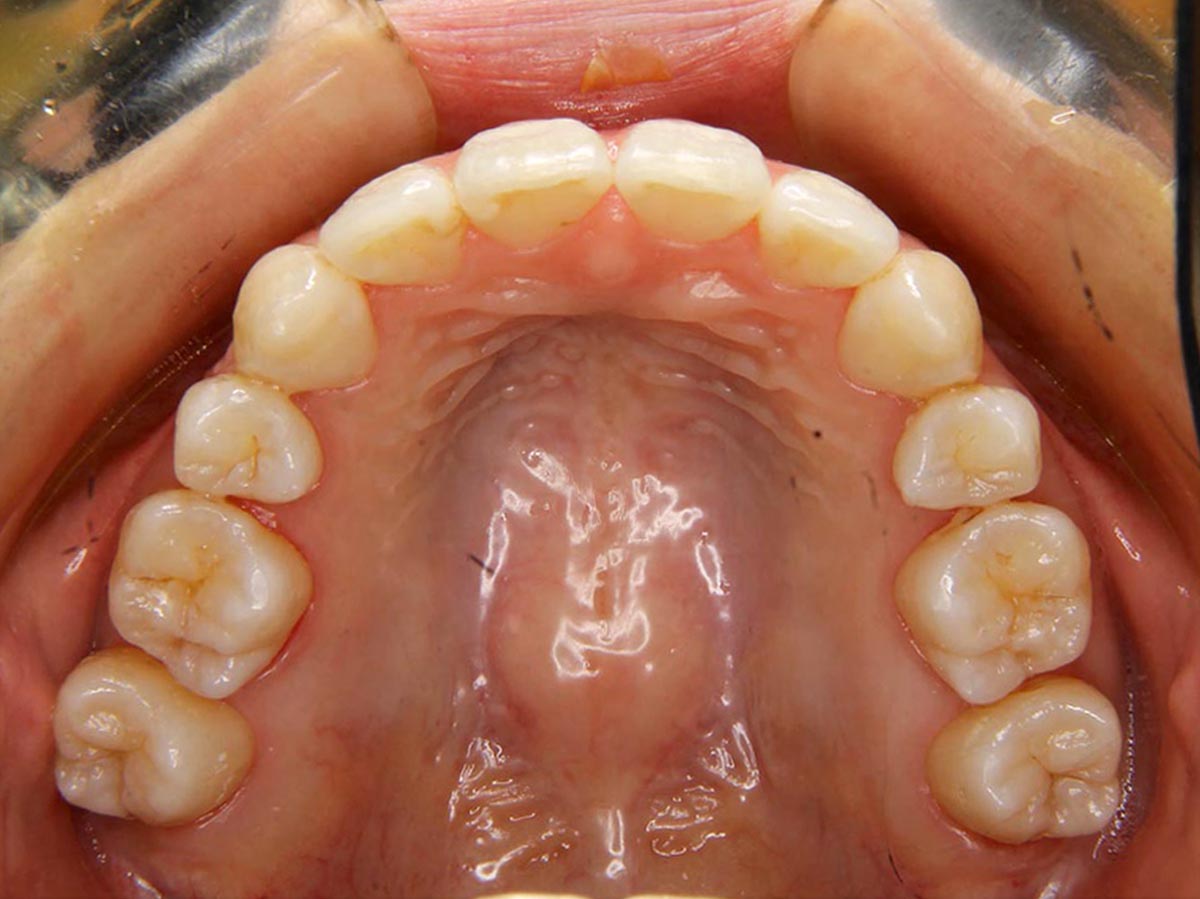

叢生(デコボコ)症例

●主訴

歯のデコボコが気になる

●診断

AngleⅠ級・前歯部叢生

●治療に用いた主な装置

上下顎にマルチブラケット装置(表側装置)

●抜歯部位

上下左右第一小臼歯

●治療期間

2年5ヶ月

●治療費用

約92万円(ともに税込、調整費、保定費まで含む総額制)

●付記

歯のデコボコを気にされおり、非抜歯にて矯正しました。